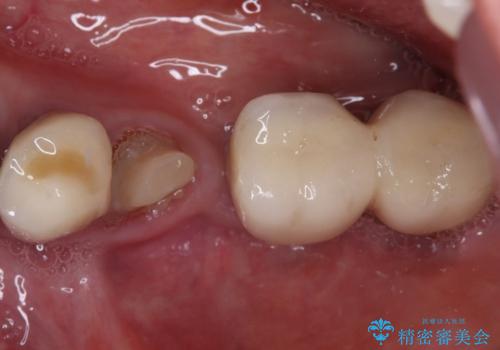

- 奥歯が割れてしまい、抜歯が必要となった患者様です。

以前にも歯が割れてインプラント治療を行いましたが、抜歯してからインプラント埋入→仮歯装着までに半年以上を要し、その間に残された歯への負担が大きくなり、左右反対側のセラミッククラウンが破折したことがありました。